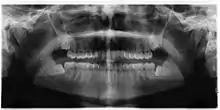

Asymptomatic disease-free impacted wisdom teeth in 21-year-old

The Cochrane review of surgical removal versus retention of asymptomatic disease-free impacted wisdom teeth suggests that the presence of asymptomatic impacted wisdom teeth may be associated with increased risk of periodontal disease affecting adjacent 2nd molar (measured by distal probing depth > 4 mm on that tooth) in the long term. Few studies, however, met the criteria to be included in the Cochrane review and those that were included provided very low quality evidence and had a high risk of bias. Another study which was at high risk of bias, found no evidence to suggest that removal of asymptomatic disease-free impacted wisdom teeth has an effect on crowding in the dental arch. There is also insufficient evidence to highlight a difference in risk of decay with or without impacted wisdom teeth.[17]

One trial in adolescents who had orthodontic treatment comparing the removal of impacted lower wisdom teeth with retention was identified. It only examined the effect on late lower incisor crowding and was rated 'highly biased' by the authors. The authors concluded that there is not enough evidence to support either the routine removal or retention of asymptomatic impacted wisdom teeth.[29] Another randomised controlled trial done in the UK has suggested that it is not reasonable to remove asymptomatic disease-free impacted wisdom tooth merely to prevent incisor crowding as there is not strong enough evidence to show this association.[30]

Due to the lack of sufficient evidence to determine whether such teeth should be removed or not, the patient's preference and values should be taken into account with clinical expertise exercised and careful consideration of risks and benefits to determine treatment.[28] If it is decided to retain asymptomatic disease-free impacted wisdom teeth, clinical assessment at regular intervals is advisable to prevent undesirable outcomes (pericoronitis, root resorption, cyst formation, tumour formation, inflammation/infection).[17]